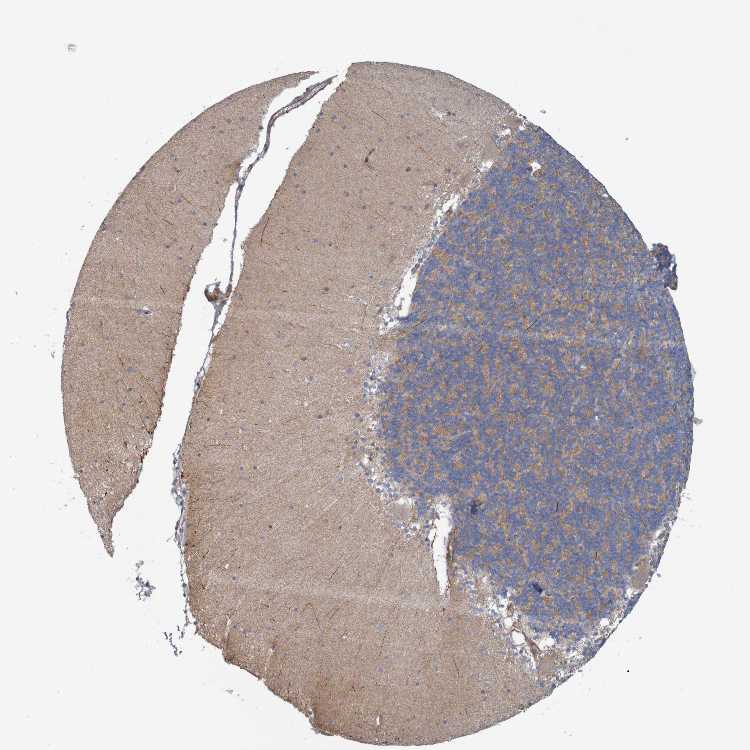

CEREBELLUM - Antibody stainingi

Antibody staining in the annotated cell types in the current human tissue is reported as not detected, low, medium, or high, based on conventional immunohistochemistry profiling in selected tissues. This score is based on the combination of the staining intensity and fraction of stained cells.

Each image is clickable and will lead to virtual microscopy that enables deeper exploration of all samples and also displays staining intensity scores, fraction scores and subcellular localization as well as patient and tissue information for each sample.

Antibody HPA012050Antibody HPA016959Antibody CAB017091

Purkinje cells LowHighNot detected

Cells in granular layer Not detectedLowLow

Cells in molecular layer Not detectedNot detectedNot detected